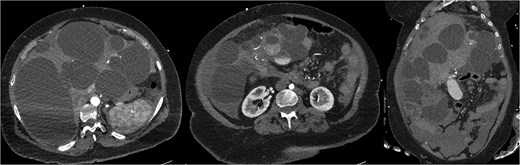

The patient initially improved but deteriorated on post-operative day 4. Repeat CTMA demonstrated active haemorrhage in segment 2—remote from the operative field—and ischaemic changes in segments 6/7, despite a patent portal vein and hepatic artery inflow (Fig. 2). Despite resuscitative measures there were increasing vasopressor requirements, leukocytosis, and deteriorating liver function tests (bilirubin 135 μmol/L, ALP 667 μ/L, GGT 551 μ/L, ALT 234 μ/L, AST 535 μ/L). Differential diagnoses included biliary sepsis, secondary infection of ischaemic liver, ischaemic hepatopathy with progressive liver failure, and angiography complications such as arterial dissection flap. Angiography failed to demonstrate active haemorrhage for an embolization target and CT liver triple-phase showed increased intrabdominal free fluid.

Repeat CTMA with arterial enhancement within the left hepatic lobe (arrow, left image), appearing more ill-defined with contrast pooling on delayed phase (arrow, right image) suggestive of active haemorrhage.